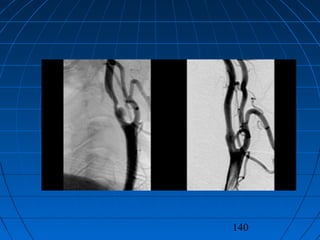

TIKAYICI SEREBROVASKÜLERTIKAYICI SEREBROVASKÜLER

HASTALIKLARHASTALIKLAR

NÖROŞİRURJİKAL YAKLAŞIMNÖROŞİRURJİKAL YAKLAŞIM

 Dekompressif kranyotomiDekompressif kranyotomi

 Karotid endarterektomiKarotid endarterektomi

 Ekstrakranyal - intrakranyalEkstrakranyal - intrakranyal

bypassbypass